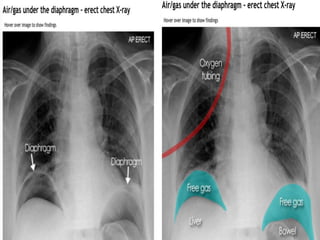

PNEUMOPERITONEUM

CAUSES:

Bowel perforation

Insufflation of gas (CO2 or air)

during laparoscopy.

Abdominal X-ray

 Although the erect chest X-ray is a much more

sensitive investigation for pneumoperitoneum,

there are several signs that may be useful in

detecting free gas on an abdominal X-ray.